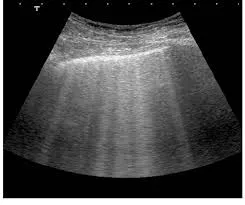

TC ou RM com contraste podem identificar novo cisto complexo, mas geralmente não diferenciam sangue de pus no interior do cisto.

Achados como realce de parede, espessamento, gás intralesional ou alterações inflamatórias pericísticas aumentam a probabilidade de infecção.

📚 Na série de casos da imagem abaixo (**[link](https://link.springer.com/article/10.1007/s40336-017-0261-8)**), é possível ver como o PET/CT-FDG orienta a conduta e modifica o manejo em infecções renais e hepáticas na DRPAD.